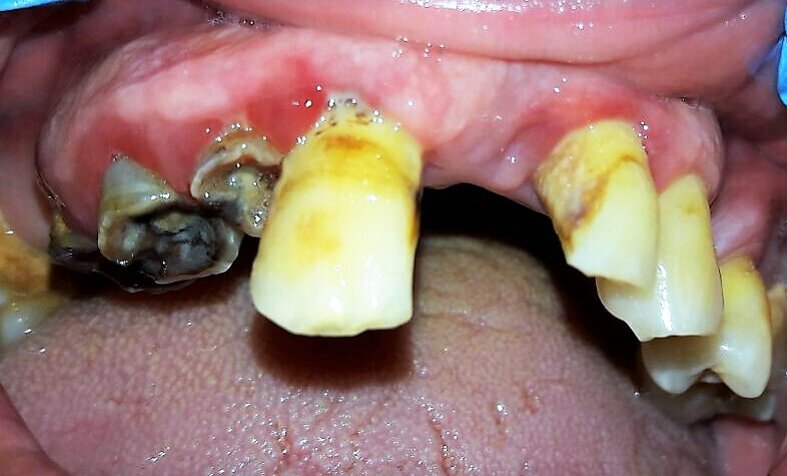

Descriviamo il caso di un paziente maschio di 56 anni con diagnosi di parodontite moderata generalizzata (Figg. 1-3), affetto da Diabete Mellito II in fase di scompenso (HbA1C 8,4%). Oltre alla malattia diabetica diagnosticata da 12 anni, il paziente presentava in anamnesi insufficienza renale, pregresso infarto miocardico acuto e storia di ipertensione arteriosa. I dati anamnestici hanno guidato la scelta dell’iter terapeutico da parte del team odontoiatrico.

In sede di valutazione clinica, il paziente presentava una scarsissima igiene orale e si evidenziavano evidenti segni di flogosi gengivale a causa di notevoli depositi di tartaro sopragengivale e sottogengivale, che rendevano difficoltoso un accurato esame parodontale. Successivamente, si è proceduto alla discussione in team circa la necessità di un intervento terapeutico personalizzato ed efficace che prendesse anche in esame la scarsa disponibilità emotiva e psicologica del paziente ad affrontarlo. Nel presente caso clinico l’adherence è stata considerata come un processo in continuo divenire. Adottando un approccio mutuato dal metodo biopsicosociale5 in una fase preliminare, un primo colloquio è stato svolto con il coniuge del paziente, al fine di instaurare un percorso riabilitativo di salute orale che fosse supportato anche dal caregiver.